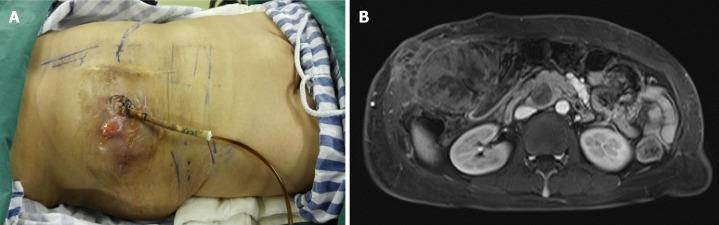

We report a case of BP with malignant transformation in a 52-year-old female patient who presented with emaciation, severe malnutrition, and a T-tube for biliary drainage that was placed for almost 2 years at the time she visited us. The enhanced magnetic resonance imaging of the upper abdomen revealed a neoplasm with a diameter of 15 cm located in the gallbladder area surrounding the common bile duct where a drainage tube was placed. It was the first case with malignant BP involving multiple organs and the abdominal wall and receiving a radical resection. Plastic surgeons helped close the incision by transferring the rectus muscle and external oblique muscle flap. A diagnosis of papillary carcinoma with diffuse malignant papillomatosis of the biliary duct was given. The postoperative course was uneventful and she was asymptomatic and in good physical condition at 35 mo postoperatively with appropriate chemotherapy.